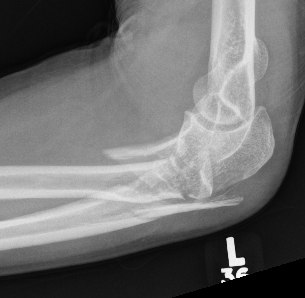

Simple Monteggia fracture - dislocations

Definition

Proximal ulna / olecranon fracture

- posterior radial head dislocation most common in adults

- no fractures

Bado Type II most common in adults with posterior radial head dislocation